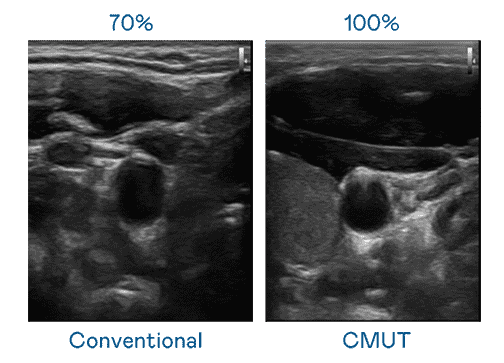

CMUT 技术是一种用电容式微机电元件来产生超音波讯号的技术。。与传统 PZT 压电式技术相比,,,,CMUT 频宽增加 30%,,更宽频的超音波讯号让影像解析度大幅提升,,,,是实现高影像品质医疗超音波扫描、、促进精准医疗发展的关键技术。。

超音波影像的解析度高低,,首先取决于探头能发出的讯号频宽。。OBPay CMUT 可提供高清晰的超音波讯号,,提供高频宽、、高灵敏度、、、影像纹理细节更高的超音波影像,,协助医护人员缩短影像判读时间及利用精准的医疗影像进行诊断。。。